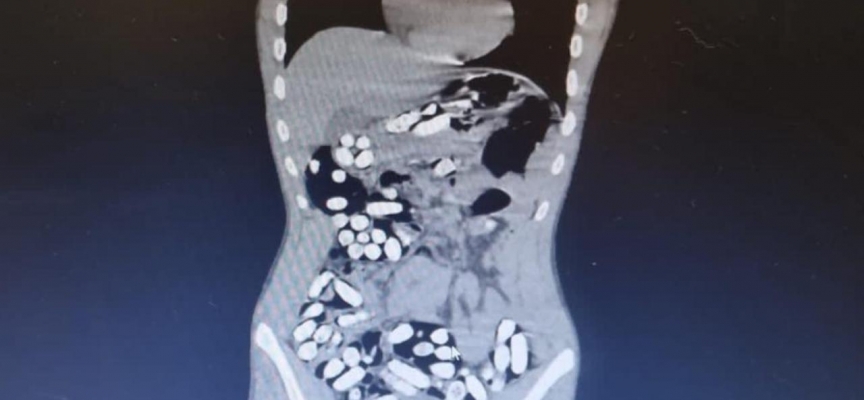

Çekilen röntgen filmlerinde şüphelilerin vücutlarında 62 kapsül eroin ve 210 kapsül afyon sakızı olduğu tespit edildi.

İç organlarının her tarafına yayıldığı belirlendi

Röntgen çekimlerinde uyuşturucu kapsüllerinin şüphelilerin neredeyse iç organlarının her tarafına yayıldığı belirlendi.

Doktor ve polis, vücutta tek seferde bu kadar yüklü miktarda uyuşturucu görmenin şaşkınlığını yaşadı.

Yapılan kontrollerde ve röntgen çekimlerinde, şüphelilerin vücutlarından 411 kapsül afyon sakızı olduğu belirlendi.